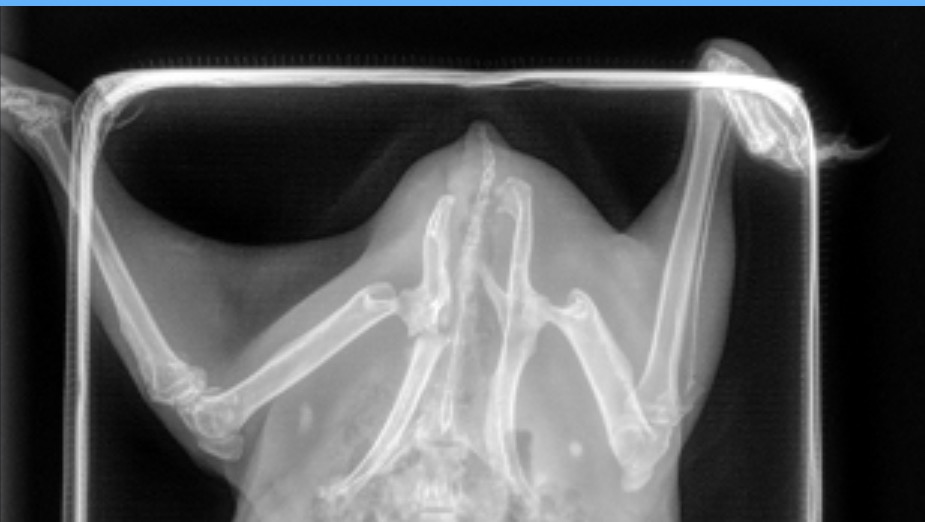

Thora’s story is heartbreaking. She was brought to me after someone admitted that they had intentionally dumped her outside. I called animal control and when the officer picked her up, she was underweight, struggling to walk, and clearly in pain. I brought her to an emergency vet right away, and x-rays showed that her pelvis is fractured in multiple places.

So far, her emergency care has already cost over $1,000. This includes sedation, radiographs, IV fluids, pain medications, and the emergency exam. She will continue to need ongoing veterinary visits and pain control.